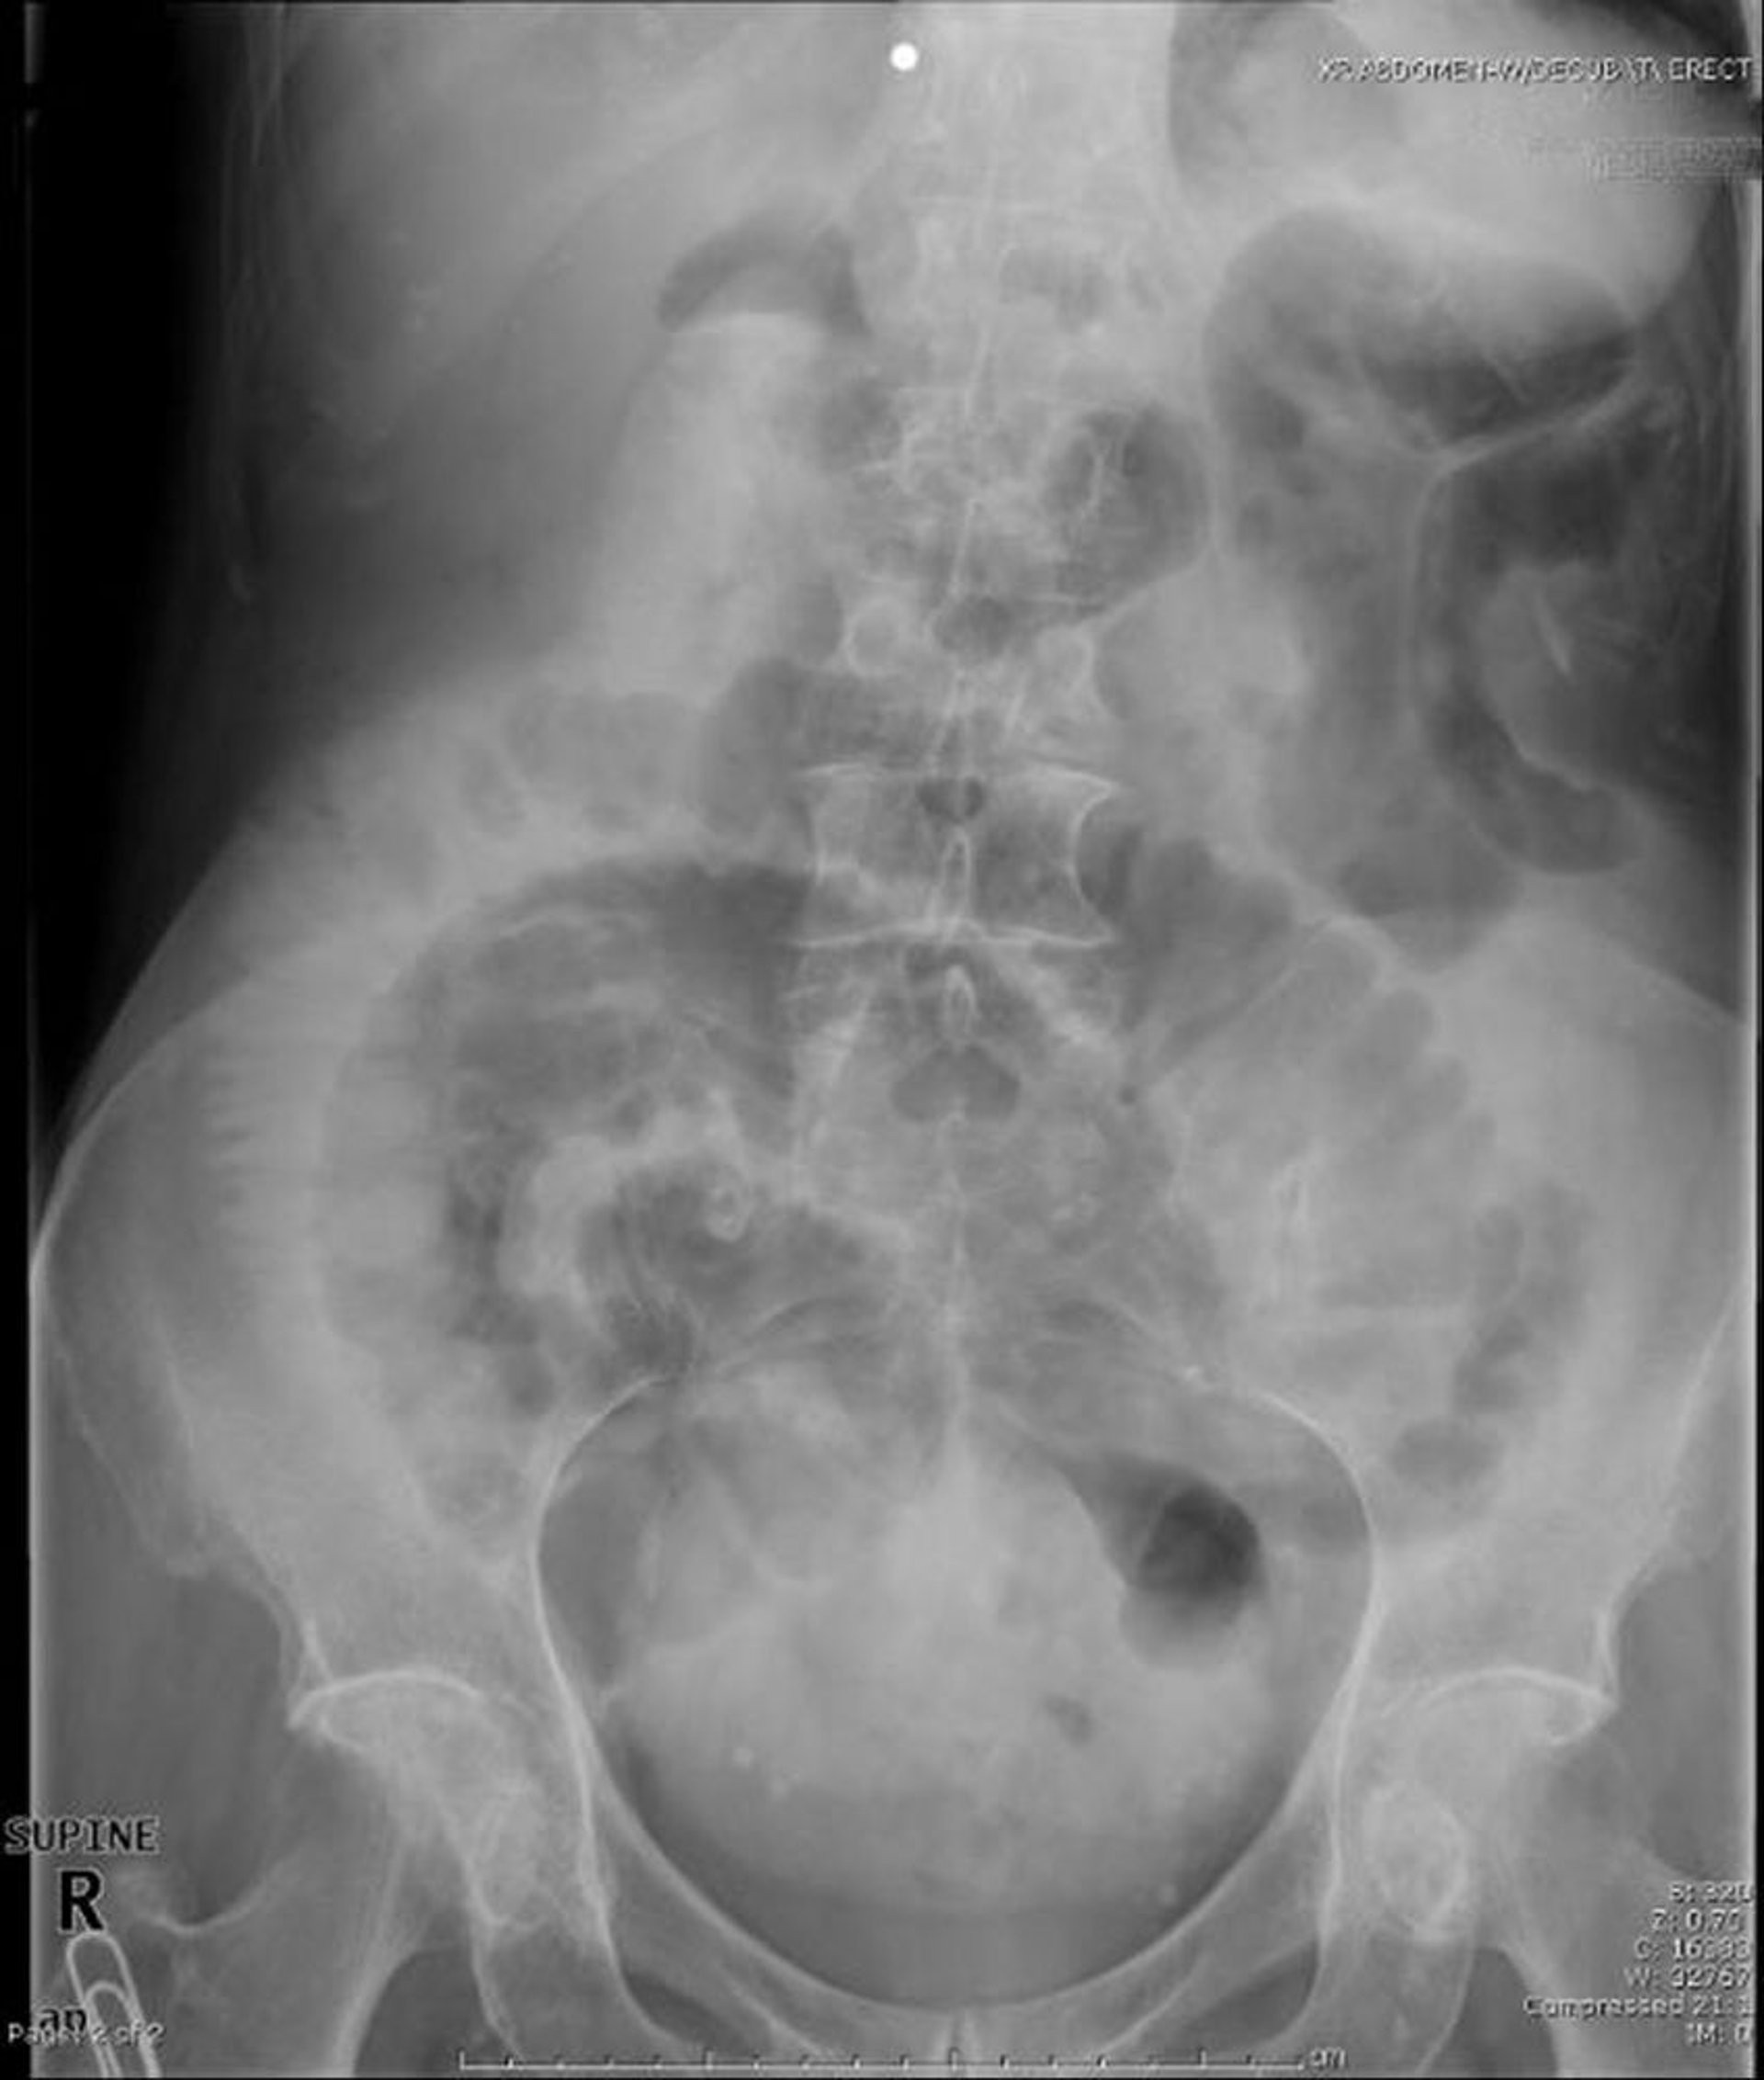

Obstrucción de intestino delgado (radiografía en decúbito supino)

En esta radiografía abdominal con el paciente en decúbito muestra obstrucción del intestino delgado. Obsérvense las asas dilatadas del intestino delgado.